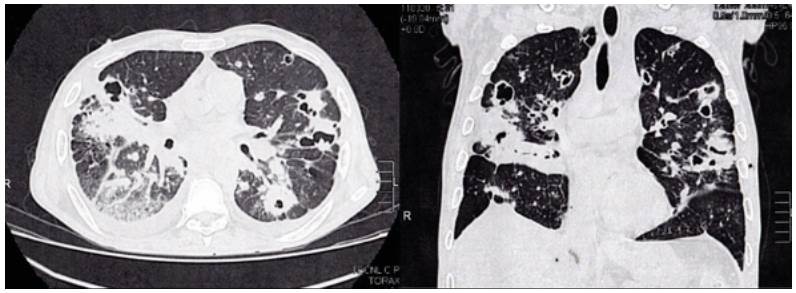

High-resolution computed tomography (HRCT) of the chest was performed (Figure 2), which showed multiple cavitations, mostly thin-walled, and randomly distributed nodules with a predominantly right pleural effusion.

High-resolution computed tomography of the chest.

Figure 2: High-resolution computed tomography of the chest.

Chest scans are the main tool to suspect this infection. Findings are nonspecific and include diffuse micronodular infiltrates predominantly in the middle zone of the lung, cavitations and tumor masses 5,14,15. Chest radiography shows mainly interstitial opacities (nodular or reticular), and when caverns are observed, pulmonary tuberculosis is the main differential diagnosis. 15,16. In high-resolution chest tomography, untreated PCM findings are characterized by attenuation of the ground-glass lung parenchyma associated with small centrilobular nodules, cavity nodules, large nodules, and scar emphysema 5,15,16, being the peripheral and the posterior distributions in the lung predominant 16. The reversed halo sign is observed in about 10% of cases 16.